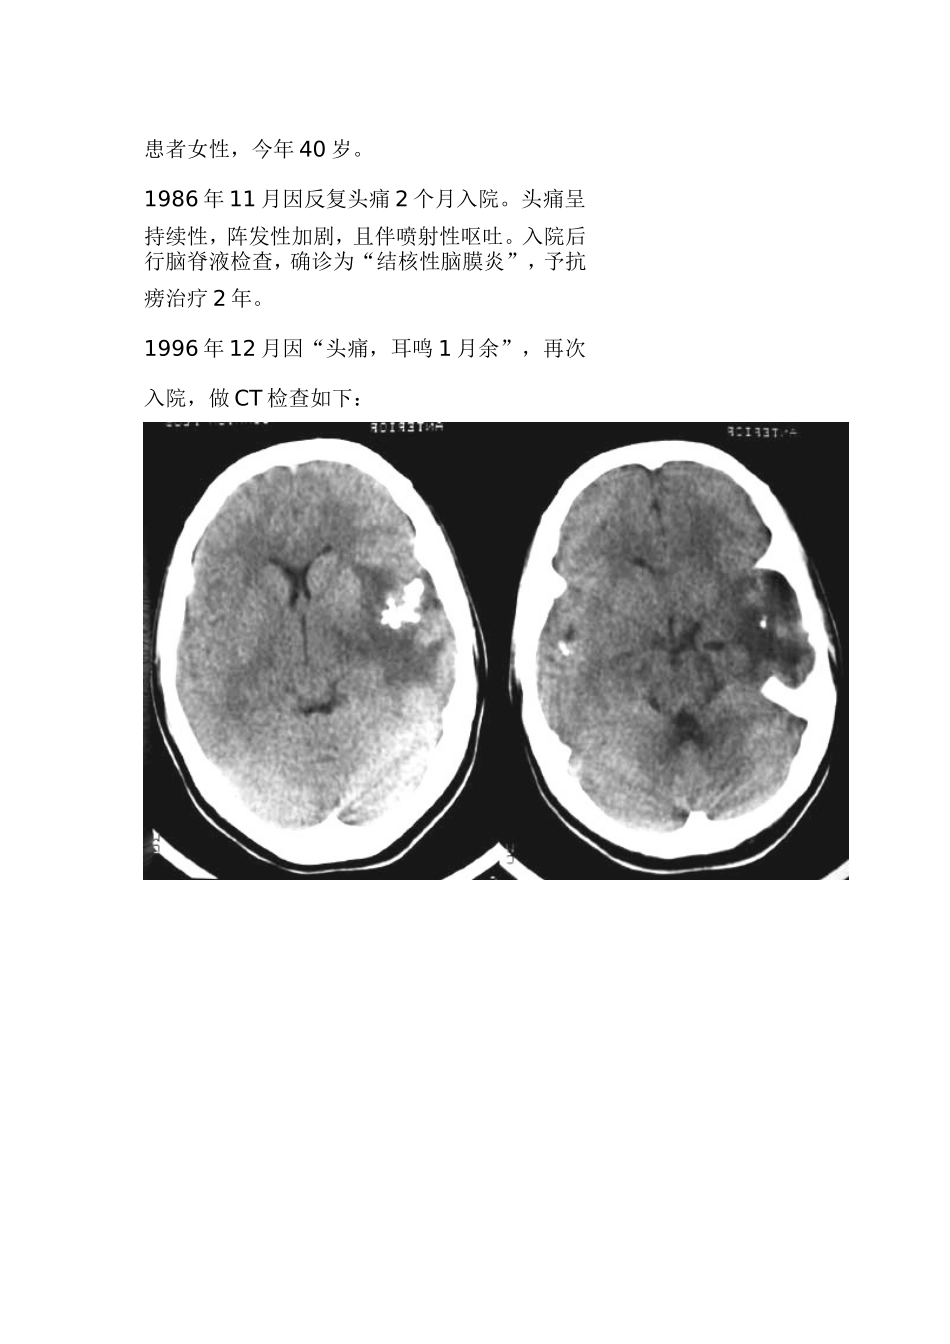

患者女性,今年40岁。1986年11月因反复头痛2个月入院。头痛呈持续性,阵发性加剧,且伴喷射性呕吐。入院后行脑脊液检查,确诊为“结核性脑膜炎”,予抗痨治疗2年。1996年12月因“头痛,耳鸣1月余”,再次入院,做CT检查如下:该例主要为脑结核与少突胶的鉴别,病人10年前有脑结核病史,现CT发现左侧颞叶条索状高密度钙化灶,周围可见片状低密度水肿带,右侧裂同样可见小结节状高密度钙化影,双侧钙化部位均位于侧裂附近,故应考虑脑结核可能性较大,再者;少枝多在额叶,钙化也额叶多见,而此病钙化是在脑池——基底池里。但钙化结节周围水肿较大,且病人病史超过10年,十年后不可能是因为结核病变而出现大面积脑水肿存在,故一不能完全排除少突胶存在。结果:手术所见:左大脑中动脉周围有约4x4x3cm范围钙化及胶质增生样改变。予以大部切除。左大脑后动脉内侧尚有少量钙化,与血管粘连紧密不能切除。病理诊断:嗜酸性肉芽肿。